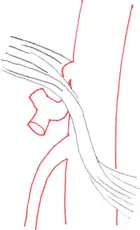

| Median arcuate ligament syndrome results from compression of the celiac artery by the median arcuate ligament. The median arcuate ligament is a fibrous arch formed by the left and right diaphragmatic crura, visible here on the underside of the diaphragm. | |

The median arcuate ligament is a ligament formed at the base of the diaphragm where the left and right diaphragmatic crura join near the 12th thoracic vertebra. This fibrous arch forms the anterior aspect of the aortic hiatus, through which the aorta, thoracic duct, and azygos vein pass. The median arcuate ligament usually comes into contact with the aorta above the branch point of the celiac artery. However, in up to one quarter of normal individuals, the median arcuate ligament passes in front of the celiac artery, compressing the celiac artery and nearby structures such as the celiac ganglia.[2] In some of these individuals, this compression is pathologic and leads to the median arcuate ligament syndrome.[2]

Further evaluation and confirmation can be obtained via angiography to investigate the anatomy of the celiac artery.[5] Historically, conventional angiography was used, although this has been largely replaced by less invasive techniques such as computed tomography (CT) and magnetic resonance (MR) angiography.[2][5] Because it provides better visualization of intra-abdominal structures, CT angiography is preferred to MR angiography in this setting.[5] The findings of focal narrowing of the proximal celiac artery with poststenotic dilatation, indentation on the superior aspect of the celiac artery, and a hook-shaped contour of the celiac artery support a diagnosis of MALS.[2] These imaging features are exaggerated on expiration, even in normal asymptomatic individuals without the syndrome.[2]

Proximal celiac artery stenosis with poststenotic dilatation can be seen in other conditions affecting the celiac artery.[2] The hook-shaped contour of the celiac artery is characteristic of the anatomy in MALS and helps distinguish it from other causes of celiac artery stenosis such as atherosclerosis.[2] This hooked contour is not entirely specific for MALS however, given that 10–24% of normal asymptomatic individuals have this anatomy.[2]